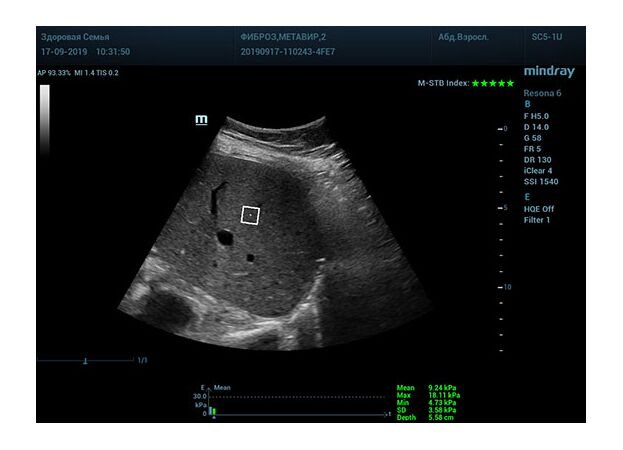

Стадия фиброза определяется по системе METAVIR Staging, построенной на данных биопсии и сопоставлении с данными эластографии. Своевременная диагностика фиброза, и начало его лечения, залог благоприятного исхода заболевания.

• METAVIRF2 – Портальный фиброз с вовлечением нескольких перегородок